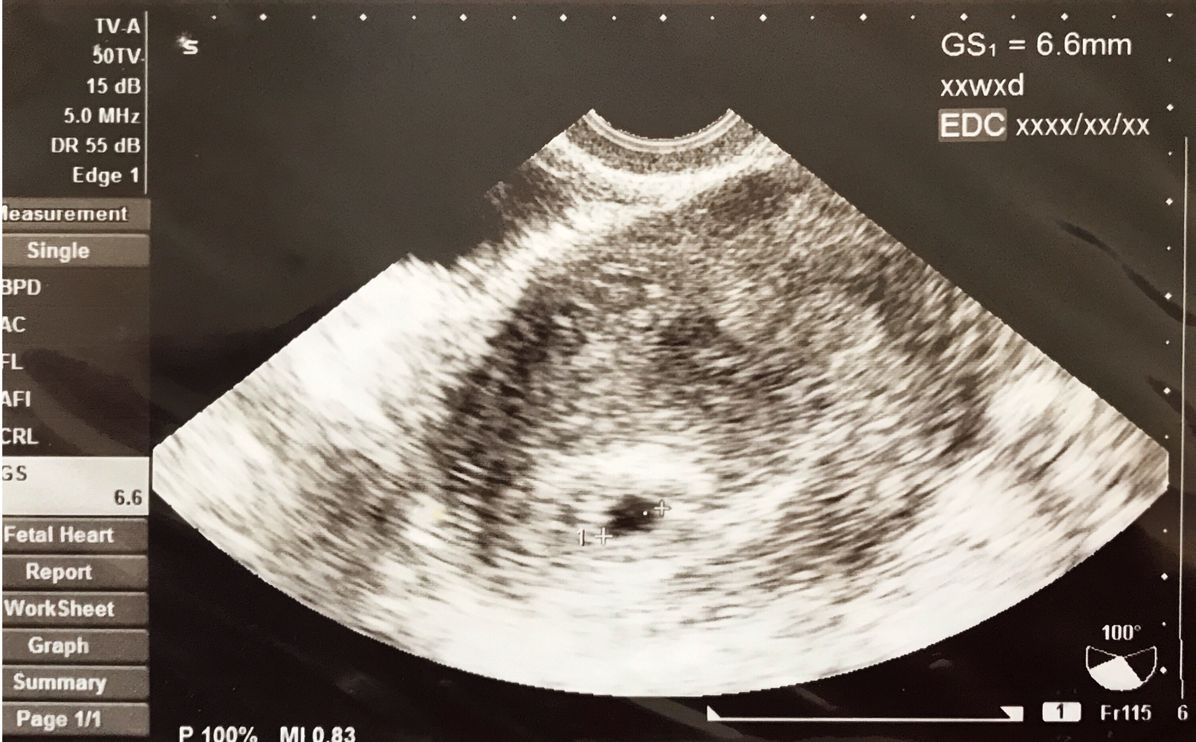

1年前娘はいませんでした。

※最初に撮った娘の写真 iPhone 7 Plus

特にそう感じるのは、娘の存在。

去年の今頃には、文字通り影も形もありませんでした。

1年あれば(正確には40週程度)、子どもが生まれてくるわけです。